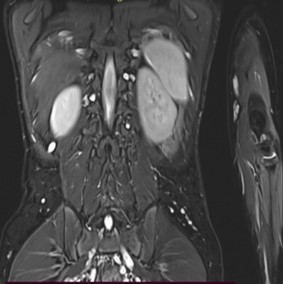

A 9-year-old male presented with a history of learning difficulties and poor scholastic performance since age six. Diagnosed with a specific learning disability-dyslexia, and Attention Deficit Hyperactivity Disorder (ADHD), he also experienced intermittent abdominal pain, enuresis, and encopresis. His development was appropriate for age. He had a borderline IQ of 75 (Wechsler Intelligence Scale for Children). He was operated for exotropia at the age six. There was no family history of neurodevelopmental or neurocutaneous disorders. Physical examination revealed short stature (Height: 128 cm, at 10th percentile), weight of 25 kg (25th-50th percentile), and a head circumference of 52 cm (50th-90th percentile). Multiple café-au-lait macules (more than 15, with only four larger than 5 mm) were noted. Dysmorphic facial features, including a flat facial profile, lowset ears, and dental malocclusion, were observed. Neurological examination was remarkable for hyperesthesia over the C6T1 dermatomes bilaterally with no other neurological deficits. Given the incomplete fulfillment of NIH criteria for café au lait macules in Neurofibromatosis Type 1, additional investigations were pursued. Slit lamp examination revealed a single iris Lisch nodule in the left eye. Both audiological and orthopedic assessments were normal. Abdominal ultrasonography and echocardiography were normal. Brain MRI identified ‘Focal Areas of Signal Intensities (FASI)’ in the bilateral globus pallidus, crus cerebri, and dentate nuclei, consistent with NF1 (Figure 1). Spinal MRI with contrast, disclosed multiple bilateral paravertebral enhancing nodular lesions in the dorso-lumbar spine and sacral canal with the largest at L4-L5 level measuring 2.6X2.4X3.2 cm in the left paravertebral region along with mild extension into the L3-L4 and L4-L5 neural foramina, consistent with plexiform neurofibromas (Figure 2). Genetic testing confirmed a heterozygous c.499del (p. Cys167ValfsTer11) pathogenic variant in the NF1 gene, affirming the diagnosis of Neurofibromatosis Noonan’s Syndrome (NFNS). The patient was initiated on methylphenidate in addition to behavioral interventions and individualized educational plan for the specific learning disability and ADHD. Neurosurgical consult for spinal plexiform neurofibromas, recommended conservative management with a trial of the novel drug, Selumetinib, a MEK inhibitor, for the spinal plexiform neurofibroma. The family received counseling on the chronic nature of the condition, the importance of close follow up, behavioral interventions for the comorbidities and the potential need for surgical intervention in the future if the spinal plexiform neurofibromas increase in size or develop a malignant transformation.

Figure 1: Coronal T1W MRI image showing focal areas of signal intensities in bilateral globus pallidi.